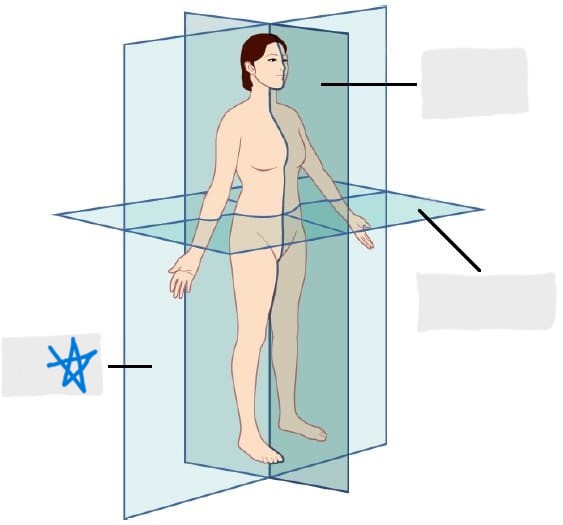

sagittal plane

frontal/coronal plane

transverse plane